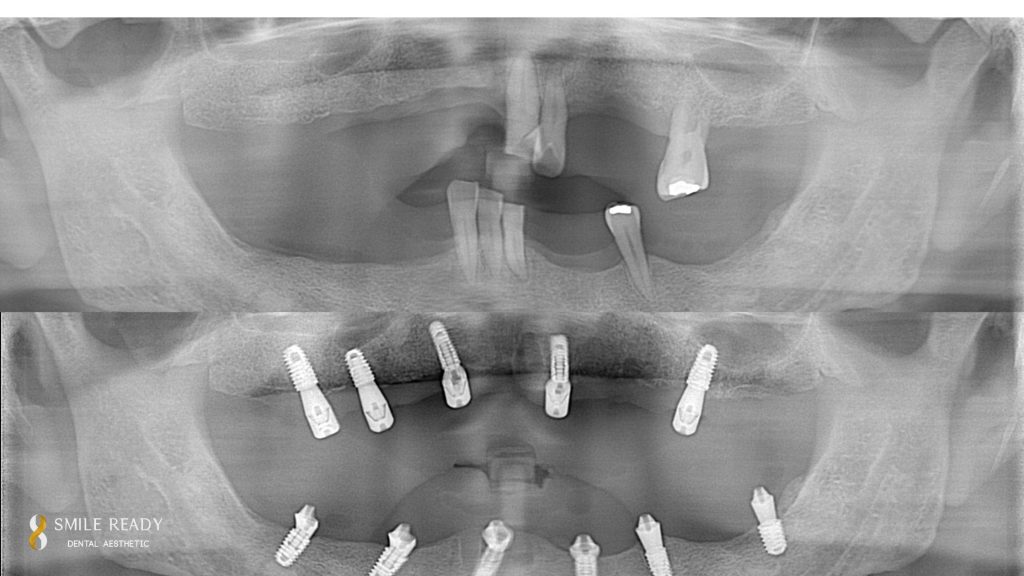

All-on-X Dental Implants: Procedure, All-on-4 vs All-on-6, Recovery & Aftercare

What is All-on-X? All-on-X dental implants are a full-arch restoration approach where a complete set of prosthetic teeth is anchored to strategically placed titanium implants, instead of placing one implant per missing tooth. The “X” refers to the number of implants used, which is customized—often four to six implants per arch depending on bone quality, […]